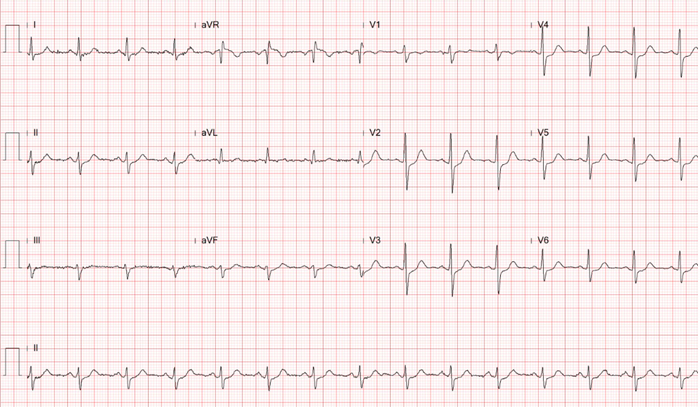

This 54-year-old businessman who had been experiencing intermittent chest pain for the past 6 months.The CCS score was II . He owns 6 factories,lives in high-stress life, combined with a smoking history of 0.5 pack per day for 10 years.Physical examination reveals chronically ill but shows neither abnormal heart sounds nor arrhythmias.Well perfusion of limbs and no pitting edema.Normal chest x-ray.EKG showed normal sinus rhythm without obvious ST changes

The laboratory test showed white blood cell count (WBC) of 7.8x10^3/uL, hemoglobin (Hb) level of 15.1gm/dl, platelet count of 181x10^3/uL.The glucose level is 98mg/dL, The liver enzyme levels show GOT (AST) at 19 U/L and GPT (ALT) at 22 U/L. Lipid panel results include HDL-C at 44mg/dL, LDL-C at 62mg/dL, triglycerides at 101mg/dL.Creatinine level of 0.75 mg/dL (eGFR:108.53) Tl-201 myocardial perfusion scan showed abnormal uptake in inferior, inferolateral, and septal wall